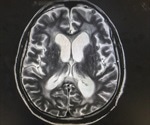

Hydrocephalus in Children

Hydrocephalus Prognosis